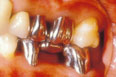

• 2. 時間が経つと,反対の歯(対合歯)が出てきます(挺出します)し,隣の歯が傾いてきます.

• 1) 食べ物が詰まりやすくなり,歯周病が進行していきます.

• 2) 歯が部分的に強くあたるようになり(早期接触,咬合干渉),咬合の異常が起こってきます.

図1